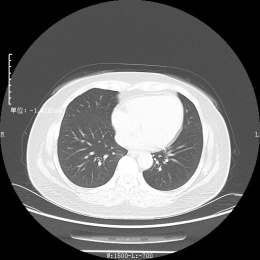

CT检查其实也是利用X射线给身体拍照片,它是为您从上到下拍很多张照片,一层一层的穿过人体检查的,因此受外物干扰小,简单来说就是看的更清晰准确

一系列照片经过计算机整合处理后,可以从多个平面观察组织结构,也可直接反映出人体骨骼的三维形态

优点:与DR相比,CT扫描出来的是断层图,器官之间无重叠且显示清晰,密度分辨率更高,可以更清晰直观地显示病变区域影像。CT检查方便、迅速而安全,且随诊方便,尤其是对于急诊病人能较快做出诊断。

缺点:CT价格高于DR,且辐射大于DR。